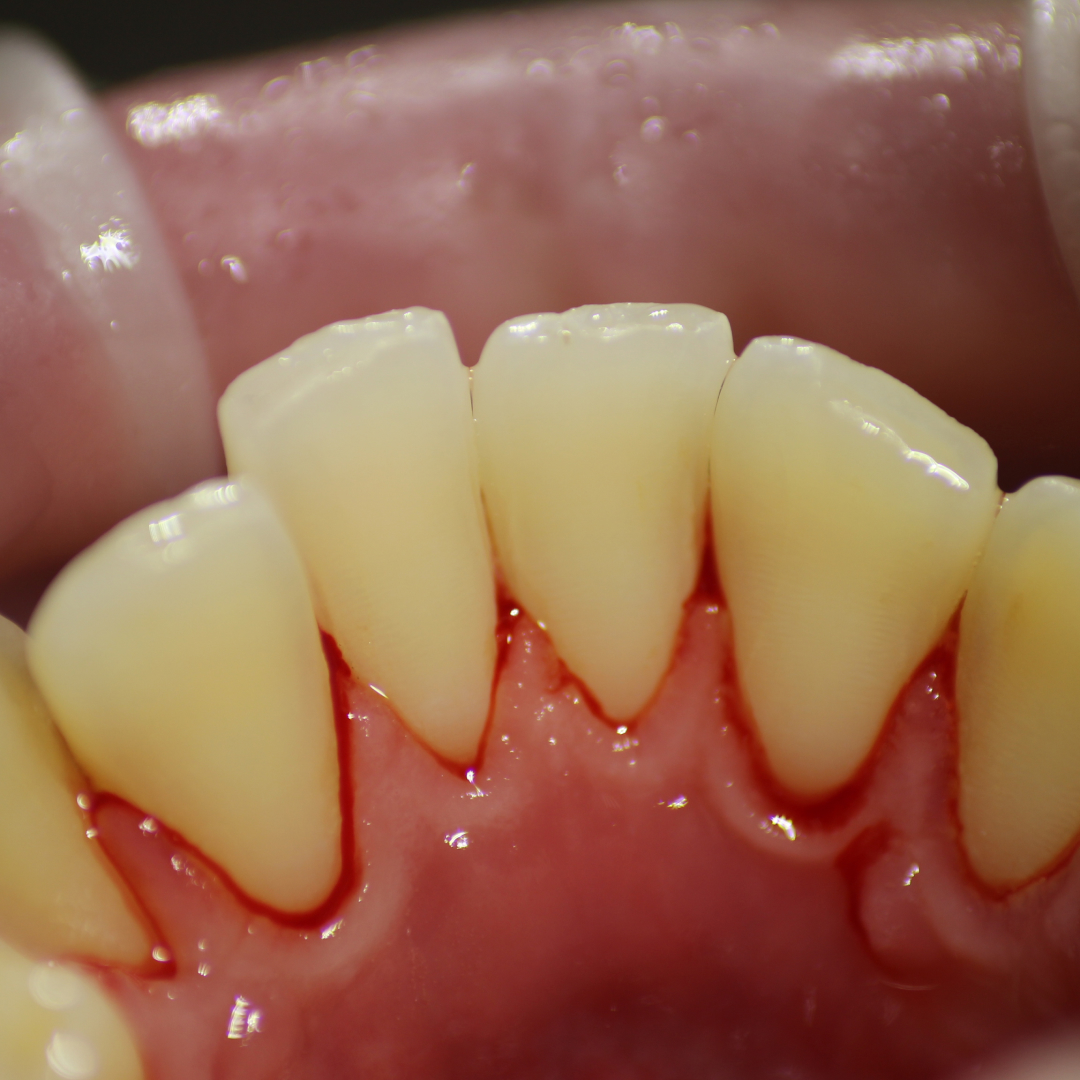

До и после лечения

В клинику обратился пациент с жалобами на кровоточивость дёсен, неприятный запах изо рта. Врач Галухина Карина Николаевна осмотрела пациента и выявила простой маргинальный гингивит. Было решено провести процедуру профессиональной гигиены полости рта. В заключение пациенту было рекомендовано использование зубной нити и ирригатора.

В ходе лечения проведены следующие работы:

- снятие минерализованных зубных отложений;

- удаление пигментированного налёта;

- полировка зубов резиновой насадкой;

- финальная полировка пастой.